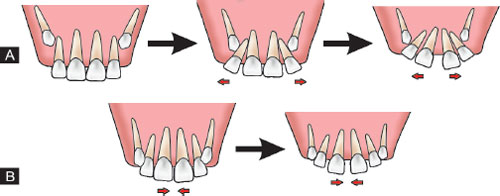

- Tooth Eruption

Gap due to eruption

The presence of the gap is not a cause of concern most of the time. It is only a cosmetic concern. The gap doesn’t cause any oral problems unless it’s occurrence is due to gum disease. The gum disease causes weakening of the tooth from the bone surrounding which causes the tooth to move causing the space in between the teeth.